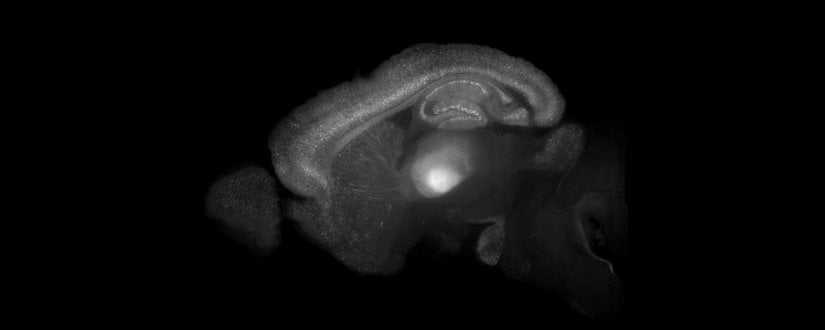

İnfantil amneziye katkı sağlayan mekanizmalardan biri, beynin dentat girus bölgesinde yaşamın erken döneminde mevcut olan yüksek nörogenez hızıdır. Dentat girusta yeni oluşturulan nöronlar (daha spesifik olarak granül hücreleri) mossy fiber projeksiyonları ile uzun-dönem belleğin en önemli bölgelerinden olan hipokampüsün CA3 bölgesinin piramidal hücreleri ile bağlantı kurar. Yeni oluşan bağlantıların entegrasyonunun daha önceden mevcut olan sinaptik bağlantılar ile yarışarak onların aktivitesini etkilediği ve hatta o bağlantıların yerine geçtiği gösterilmiştir. Bu yeniden organizasyon, bu devrelerde depolanmış bilginin kaybolmasına yol açar ve infantil amnezi fenomeninin temelini oluşturur. Yani bebeklik anılarınızı hatırlayamamanızın ana nedeni, o anıların üretildiği nöronların yerini çoktan yeni nöronlar almış olmasıdır.

İnfantil amnezi sürecinde unutulmuş görülen bu anıların tamamen kaybolup kaybolmadığını anlamak için sinirbilimciler optogenetik yöntemlerden faydalandı. Farelerde bağlamsal korku koşullanması oluşturdular. Bu eğitimde fareler belirli ipuçlarının olduğu bir ortamda ayağa elektrik şoku gibi bir koşulsuz uyarana maruz kalırlar. Fare aynı ortama tekrar yerleştirildiğinde ortamdaki ipuçlarını tanır ve korku cevabı sergiler. İnfant fareler (örneğin 17 günlük) bağlamsal korku koşullanmasını öğrenebilirler; ancak kısa bir süre içinde öğrendiklerini unuturlar. Aksine yetişkin fareler uzun süre boyunca koşullanma göstermeye devam ederler, hatta cevap gittikçe güçlenir ve bu bize belleğin konsolide olduğunu gösterir.

İnfant farelerde bağlamsal korku koşullanmasında aktive olan nöronları etiketlemek için, nöronların aktivitesi optogenetik stimülasyon ile kontrol edilebilecek bir iyon kanalı olan channelrhodopsin-2 (ChR2) ekspresyonu ile eşlendi. Bu sayede korku koşullanması sırasında aktif olan nöronların bu proteini eksprese etmesi sağlandı. ChR2 uygun dalga boyunda ışık ile uyarıldığında hücre içine Na+ akışına izin verir. Bu Na+ iyonları daha sonra hücrenin bir aksiyon potansiyeli ateşlemesini sağlar. Bu yöntem böylece, araştırmacıların hücrenin uyarılabilirliğini ışık ile kontrol etmesine olanak tanır.